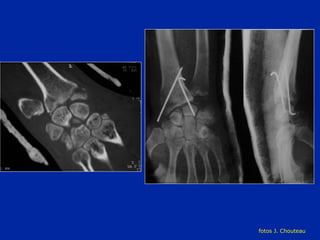

Luxación del semi lunar  Riesgo de necrosis

fotos J. Chouteau